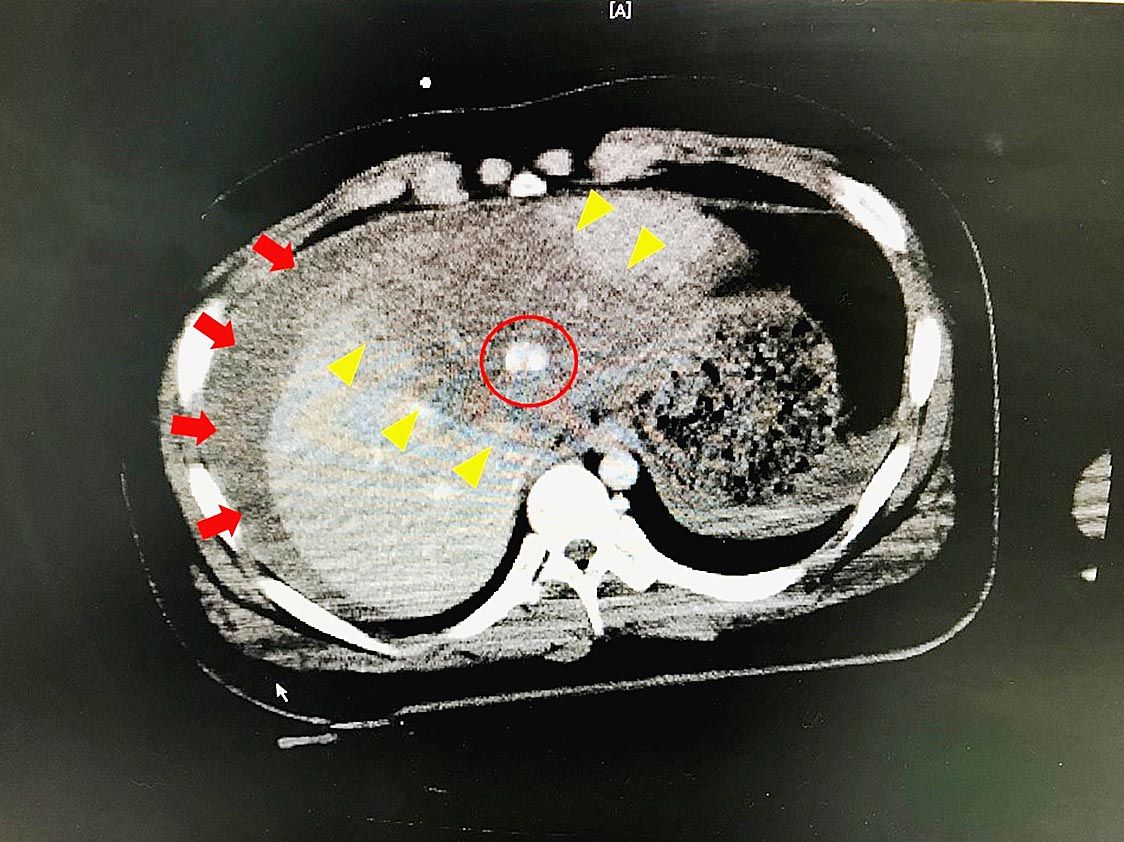

〇実質臓器損傷とは 実質臓器とは中身の詰まった臓器であり、中が空洞の管腔臓器と対をなす。具体的には肝臓、脾臓、腎臓、膵臓が腹部実質臓器である。 肝臓は右横隔膜下にあり栄養の貯蓄や合成、有害物質分解、胆汁生成など様々な機能を持つ。脾臓は左横...